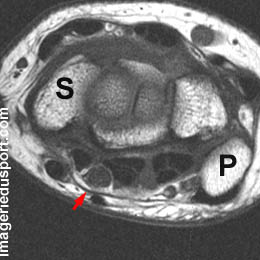

A - IRM coupe axiale T1 du poignet : Aspect ovoide du nerf médian à hauteur du Triquetrum (pyramidal).

B - IRM coupe axiale T1 du poignet : Aspect bipartite du nerf médian à hauteur de l'os crochu. Respect du rétinaculum superficiel et des tendons fléchisseurs.

Nerf médian : division précoce (asymptomatique).